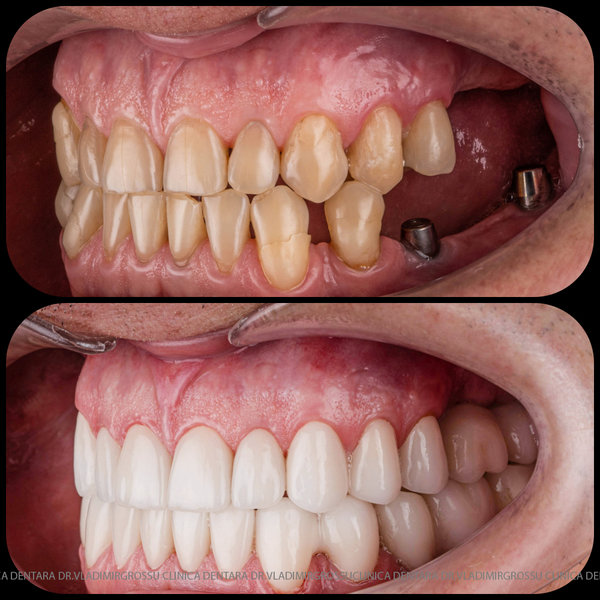

Protezarea pe implanturi dentare este soluția modernă, estetică și funcțională pentru înlocuirea dinților lipsă. Această procedură combină precizia chirurgicală cu tehnologia avansată de laborator pentru a reda pacienților zâmbetul natural, vorbirea clară și capacitatea de a mânca fără restricții.

La Clinica Dentară Dr. Grossu din Chișinău, oferim protezări pe implanturi dentare personalizate, realizate de o echipă multidisciplinară, cu ajutorul celor mai noi tehnologii digitale și materiale biocompatibile.

- Estetică superioară – imită perfect dinții naturali

- Funcționalitate completă – mestecare și vorbire fără restricții